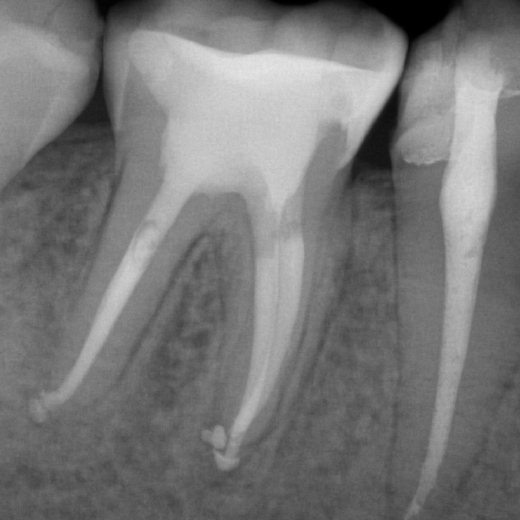

Fallbeispiel: Frontzahntraumata-Trauma im Alter von 9 Jahren mit Recall nach 22 Monaten

Frontzahntraumata sind im Kinder- und Jugendalter nicht selten. Bei noch nicht abgeschlossenem Wurzelwachstum können solche Zähne erfolgreich mit einer Revaskularisation behandelt und erhalten werden.